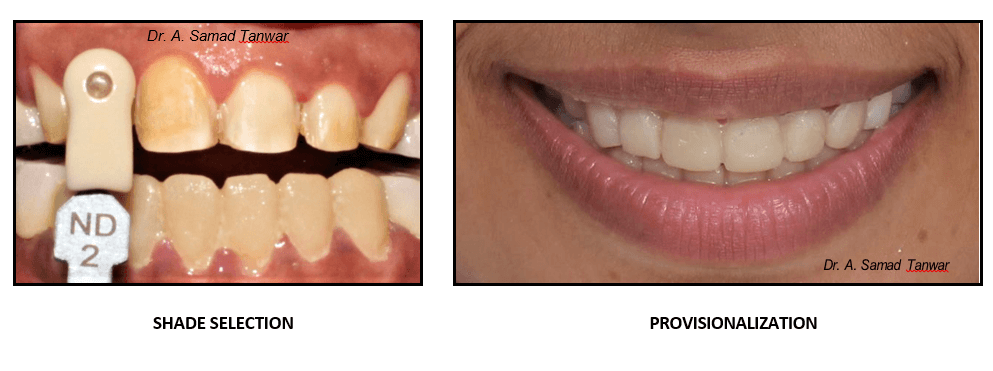

After the preparation stump shade selection was done using VITA stump shade guide.

Lithium disilicate glass ceramic was fabricated for maxillary and mandibular Lithium disilicate (Emax) is an aesthetic, high strength material that can be conventionally cemented or adhesively bond.

Lithium disilicate is among the best known glass